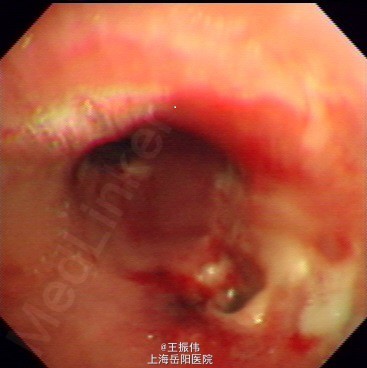

气管居中,颈静脉正常,胸廓两侧对称,无桶状胸,呼吸运动两侧对称,呼吸频率20次/分,肋间隙正常,无胸膜摩擦感。两肺叩诊清音,右肺可闻及湿性啰音,胸部CT:右肺上叶占位灶,两肺小结节灶,纵膈淋巴结增大,左肺下叶、右肺中叶炎症;两肺气肿伴肺大泡。组织病理【z155818】:灰白组织2粒,直径0.1cm。诊断:(左肺下叶开口)肉芽肿性炎,结核可能,请临床做相关病原体检测。支气管镜痰涂片:找到抗酸杆菌。

(传)肺结核,予异烟肼、利福平、链霉素等抗结核治疗。

药物治疗的主要作用在于缩短传染期、降低死亡率、感染率及患病率。对于每个具体患者,则为达到临床及生物学治愈的主要措施,合理化治疗是指对活动性结核病坚持早期、联用、适量、规律和全程使用敏感药物的原则。